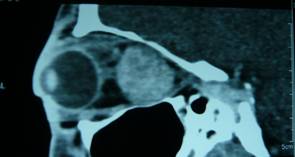

| CT scan evidencing intraconically growing hemangioma | |

- Vascular lesions: hemangiomas (the most common)